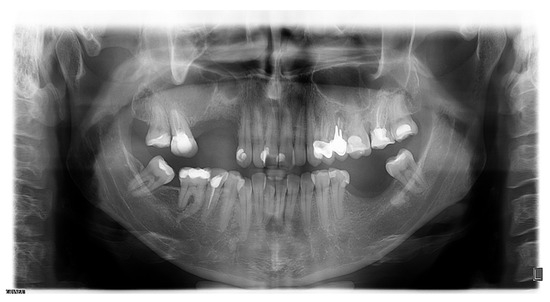

2. Case Presentation